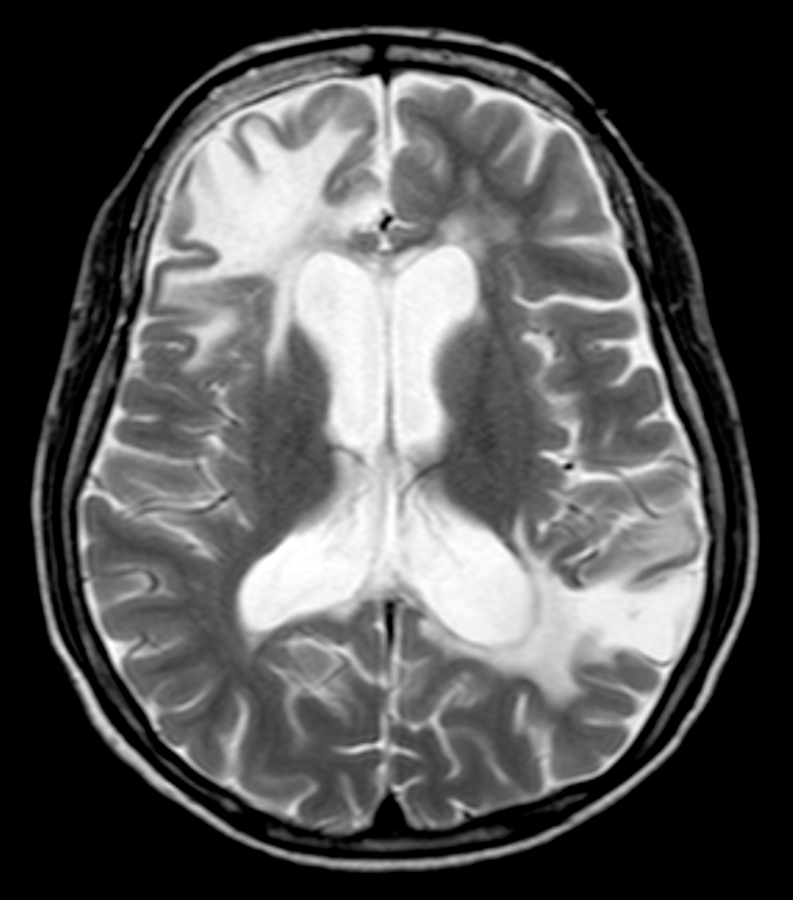

Fig. 16-5 : Neurolupus.

Imagerie par résonance magnétique (séquence T2). Hypersignaux importants de la substance blanche.